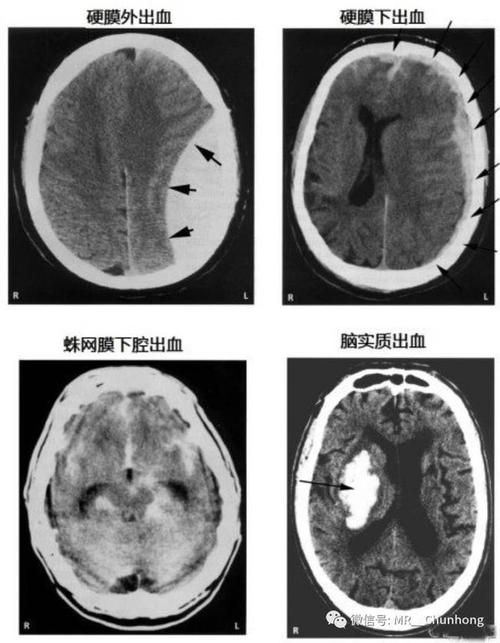

血肿范围较广,多呈新月形,可跨颅缝分布,但不跨硬膜返折如大脑镰和

硬脑膜内层形成大脑镰,因此硬膜下血肿不穿过中线,但可穿过颅缝,这与